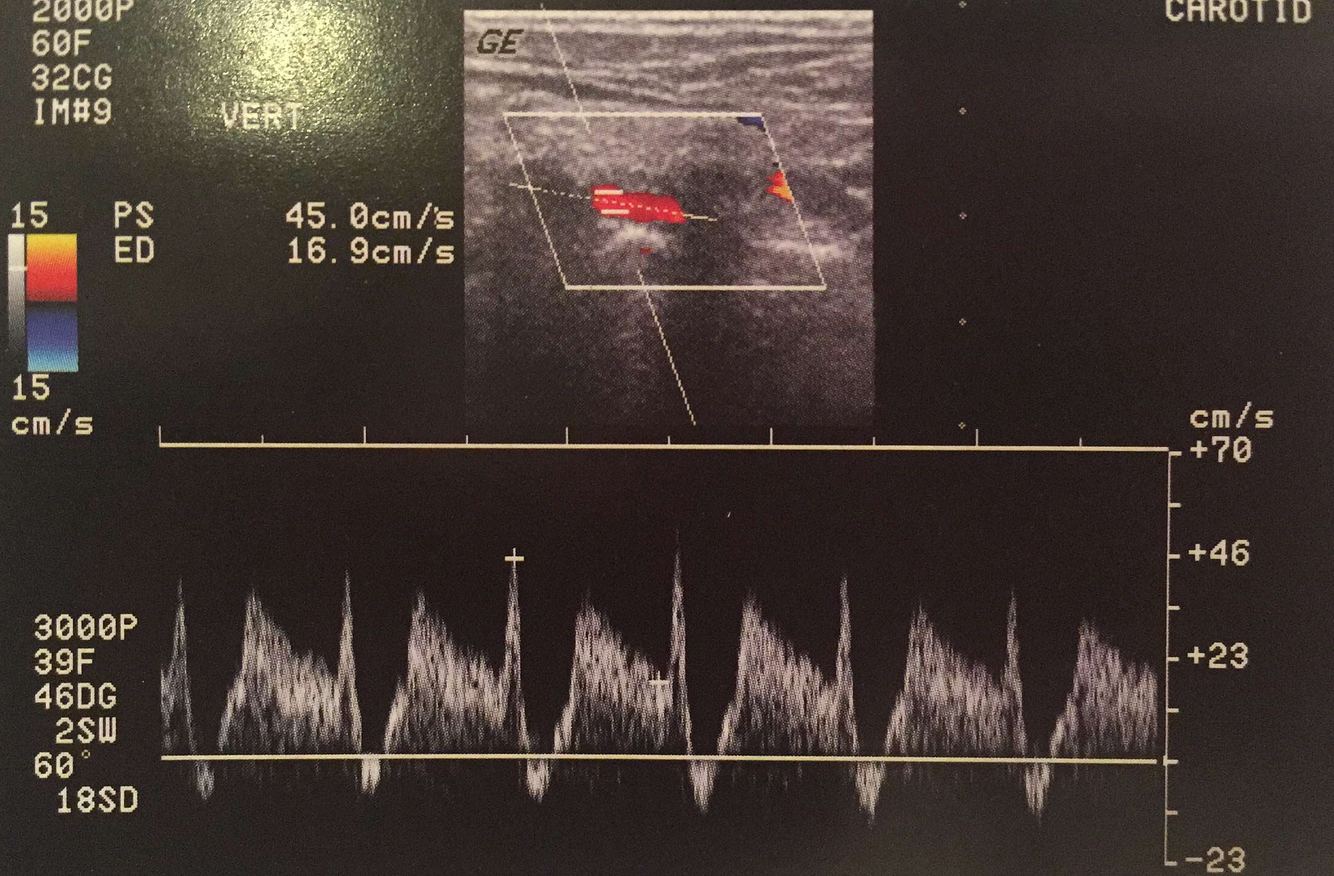

high resistance CCA waveform

stenosis in ICA or in MCA/Circle of Willis